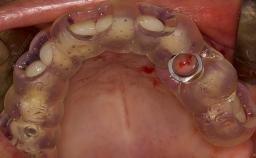

Lateral Sinus Floor Elevation

Following tooth loss, alveolar resorption and ongoing pneumatization of the maxillary sinus may lead to vertical and horizontal bone deficits in the posterior maxilla.

This deficit reduces the distance between the maxillary sinus floor and the alveolar process, so that reconstructing the vertical bone height by means of a sinus floor elevation procedure may be a prerequisite for placement of dental implants of the correct dimensions and in the ideal three-dimensional positions in order to achieve optimal functional and esthetic treatment outcomes while respecting relevant anatomical structures.